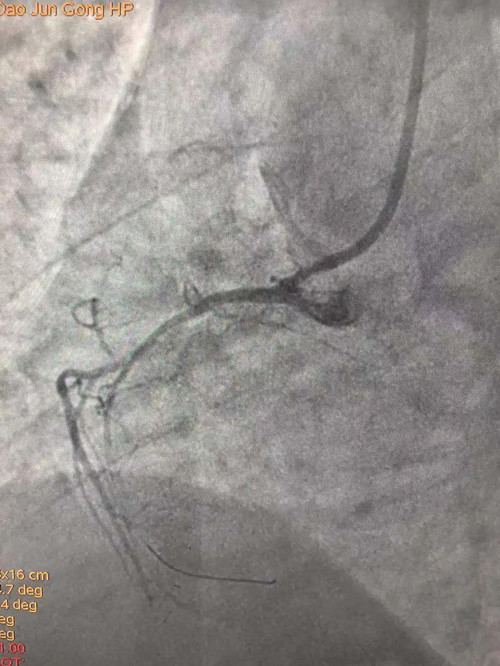

患者胸痛明显,伴有大汗,造影显示右冠近段严重百分之百闭塞,手术过程异常艰辛。重症医学科王秋艳介入团队医生应用1.5*15球囊反复小压力扩张,现在摆在医生面前的难题是既要打开血流又不能将血管扩撕,1.5球囊扩张后应用替罗非班,再次应用2.0球囊低压力持续扩张,此时显影出现右室支,患者症状立即缓解,血流恢复。由于患者右冠细小,不适合做支架,所以决定回病房继续药物治疗。